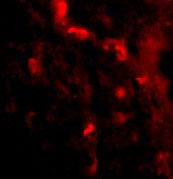

Immunofluorescence of IRGM in Human Brain tissue with IRGM antibody at 20 μg/mL. |